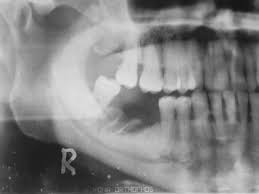

Osteonecrosis de la mandíbula relacionada con la medicación: análisis de la gama de fármacos implicados de la base de datos australiana de notificaciones de eventos adversos

Este estudio contribuye a la escasa pero creciente literatura que asocia un número creciente de fármacos con osteonecrosis de la mandíbula relacionada con la medicación (ONMRM) y subraya la importancia de considerar todos los fármacos posibles que elevan el riesgo de ONMRM de un paciente. Br J Clin Pharmacol, junio de 2021